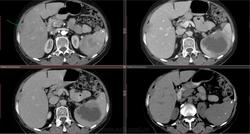

На аксиальных КТ-изображениях брюшной полости с последующими реконструкциями печень не увеличена (60X).

В S6 и S8 правой доле имеются подкапсульные образования размером 2.0*1.9 см (40Х), 1.4*0.8 см. негомогенно усиливающиеся в артериальную фазу.

Селезенка размерами 12.5*9.2*10.3 см (34Х). В ее паренхиме множество округлых образований размером до 0.8 см, плотностью 516х. В проекции ворот селезенки определяется нечетко очерченный участок низкой плотности(12Х), с неровными контурами, размером 7.3*7.7*7.4 см,

при контрастировании - гиперваскулярный по периферии.

Подкапсульно у верхнего полюса селезенки образование размером 2.4*1.7 см, у нижнего полюса размером 2.9*3.6 см, гетерогенной структурой, негомогенно усиливающиеся при контрастировании.

Поджелудочная железа - головка-тело-хвост размерами 2.2*1.9*1.8 см, денситометрическая плотность 36Х-34Х-32Х соответственно. При контрастировании определяется однородное накопление контраста 101Х-109Х-96Х.

По латеральному контуру слепой и восходящей кишки образование мягкотканной плотности, с волнистым четким контуром, размером 2.6*7.2 см, неравномерно усиливающееся после контрастирования.

На границе нисходящего отдела и сигмы образование размером 7.6*6.8 см, прорастающее переднюю брюшную стенку (38Х), так же неравномерно накапливающее контраст.

Заключение: КТ - признаки cr слепой, восходящей кишки; cr сигмы с прорастанием в переднюю брюшную стенку. Mts в селезенку и печень. Кальцинаты в селезенке. Киста правой почки.